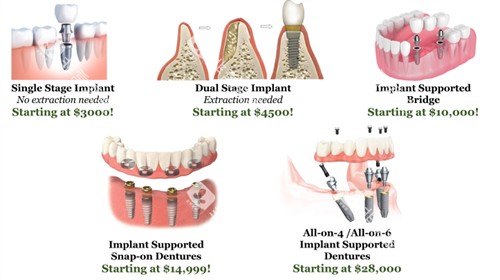

技术设备很较高

医院配备了科技智能智能化的诊疗设备,能够为患者提供更更准一些、较高的效率的口腔诊疗服务。

无论是牙齿种植时的更准一些定位,还是正畸过程中的方案设计,较高的设备都能发挥重要作用。